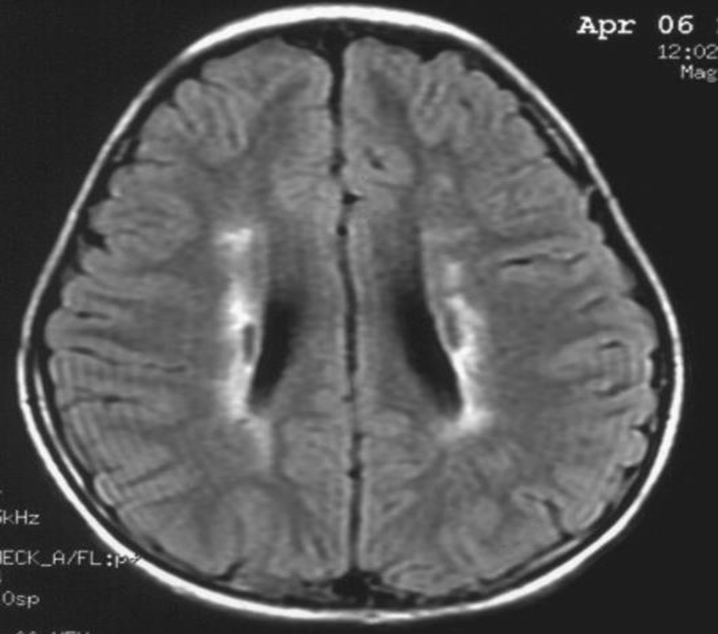

患者:林某某性別:男年齡:8 歲基本情況:出生后3個月臨床和頭部CT檢查診斷為腦癱。8年來病人曾在全國各地接受各種中西醫(yī)治療,病人入院時確診為痙攣性腦癱。治療時間:2005年7月接受干細胞移植手術(shù)。